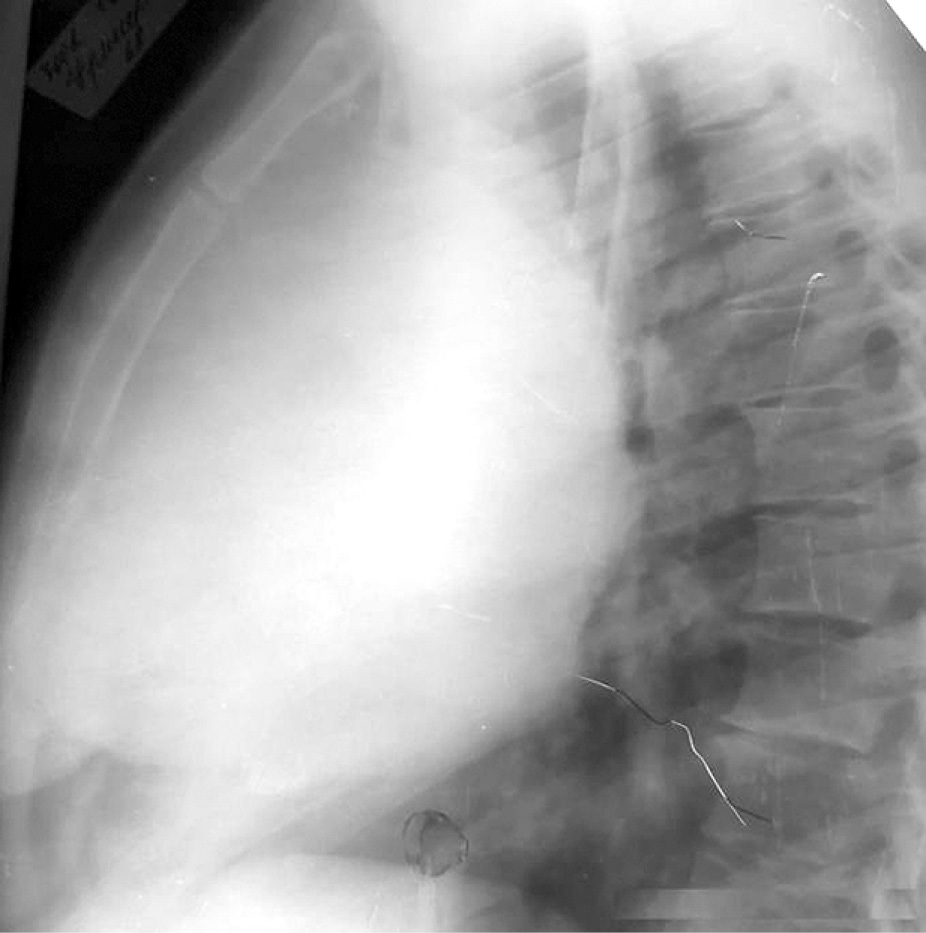

Контрольный осмотр проведён 15.04.22 г. Состояние удовлетворительное, жалоб не предъявляет. Контрольная рентгенография грудной клетки от 15.04.22 г. не выявила патологии в лёгких (рис. 4, 5). Клинические и биохимические показатели крови в пределах нормы.

Рис. 5. Контрольная рентгенография грудной клетки в правой боковой проекции через 16 лет после комплексного лечения.

Fig. 5. Control radiography of the chest in the right lateral projection 16 years after complex treatment.